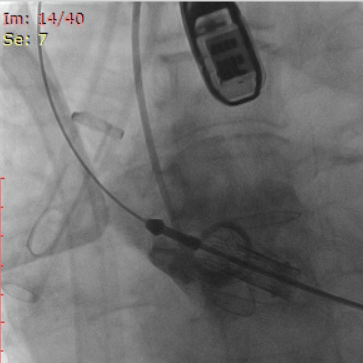

经心尖TAVR:经右侧股静脉置入临时起搏器,经右侧股动脉在患者主动脉无冠窦内放置1根6F猪尾导管进行协助定位。透视下定位后第六肋间小切口进胸,打开心包,选择心尖裸区缝制六边形荷包。心尖穿刺后将泥鳅导丝过主动脉瓣经升主动脉、主动脉弓到达降主动脉膈肌水平,通过TEE确认细导丝没有与二尖瓣腱索缠绕。单弯管交换硬导丝后,用16F扩张鞘预扩心尖穿刺处,先用24号球囊对狭窄瓣膜预扩一次(快速起搏心率:180次/分)(图3),后将 J-Valve瓣膜(25号)装入输送器,将输送器推送至主动脉根部,释放定位件,适当调整定位件角度使其进入三个主动脉窦部。通过DSA和TEE确定三个定位件准确入窦后完全释放瓣膜,撤出输送器。快速起搏心率180次/分,用24号球囊后扩一下人工瓣。通过DSA和TEE观察人工瓣膜膨胀后金属支架的形态、位置良好,无瓣周漏,前向血流速度较术前明显降低(图4-6)。撤出球囊及导丝,收紧心尖处荷包线并打结,后鱼精蛋白中和肝素,彻底止血,逐层关胸,封皮,拔出股动脉鞘并在股动脉穿刺处压迫止血。手术过程顺利,患者生命体征平稳。

图3.术前24号球囊预扩